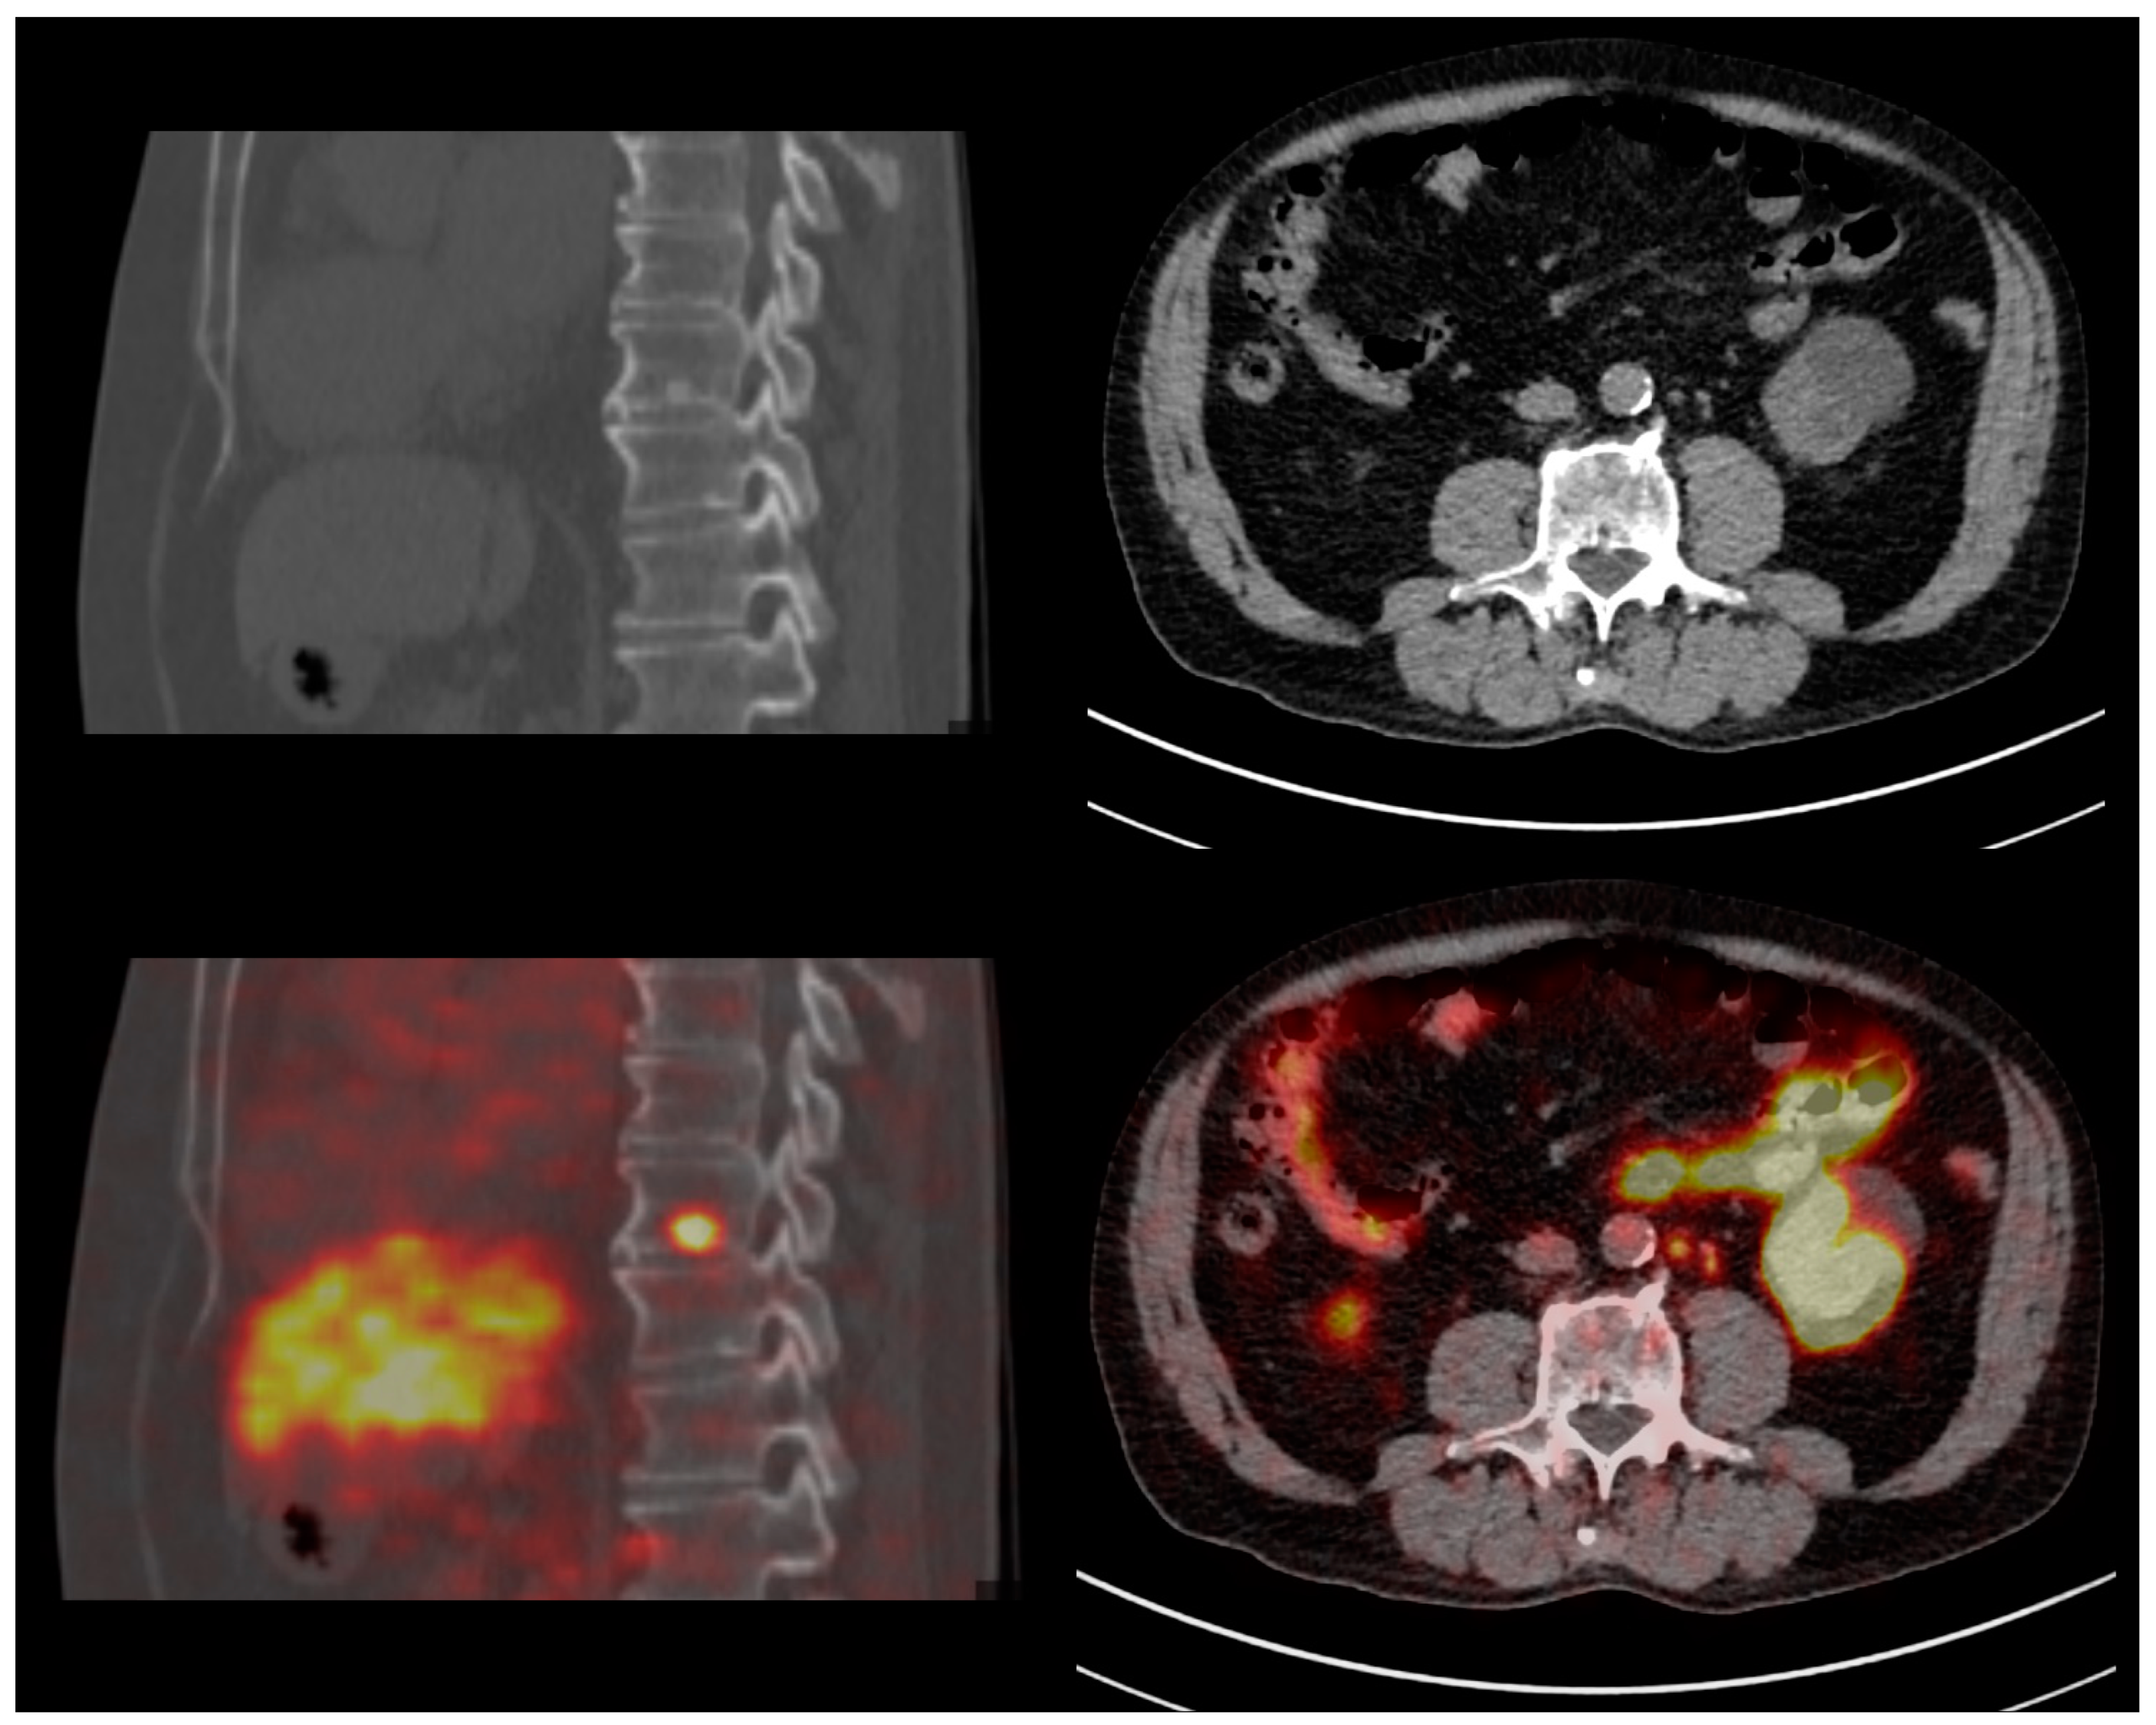

Regarding PET semi-quantitative analysis, the median SUVmax values of the lesions (PSMA-RADS ≥ 3) and reference regions (blood pool, liver, salivary glands) were higher at dPET compared to aPET: lesions SUVmax (5.0 [3.3–9.0] vs. 3.1 [2.0–5.7]), blood pool SUVmax (2.1 [1.8–2.3] vs. 1.3 [1.2–1.6]), liver SUVmax (7.6 [6.4–9.3] vs. 5.9 [5.0–6.9]), salivary glands SUVmax (19.8 [15.2–23.1] vs. 14.3 [11.9–18.5]) (all p-values < 0.001). Finally, the median lesion-to-blood-pool SUVmax ratio was comparable (even after PSMA-RADS stratification) between dPET and aPET (2.6 [1.7–4.3] vs. 2.3 [1.5–4.0], p = 0.2), but dPET identified nodal metastases with a smaller maximum diameter compared to aPET (PSMA-RADS 4 miN1/M1a: 5 [IQR: 4–7] vs. 7 [IQR: 5–8] mm, p = 0.002). Figure 3 illustrates the findings from two PCa patients restaged with PSMA dPET for early BCR (PSA 0.2 ng/mL).

Figure 3.

Clinical cases—Restaging of two early-recurrent prostate cancer patients with digital PSMA-PET/CT. Left column: 73 yo patient with Gleason 9 (4 + 5) pT3bN1 prostate cancer, treated with radical prostatectomy + linfadenectomy (03/2017) and salvage RT (07/2017); biochemical recurrence with PSA 0.23 ng/mL. PSMA-PET/CT identified a vertebral (D9) osteoblastic metastasis with intense tracer uptake. Right column: 75 yo patient with Gleason 9 (4 + 5) pT3bN1 prostate cancer, treated with radical prostatectomy and linfadenectomy (01/2019); biochemical recurrence with PSA 0.22 ng/mL. PSMA-PET/CT identified multiple extra-pelvic (para-aortic) subcentimeter nodal metastases (maximum diameter: 5 mm).